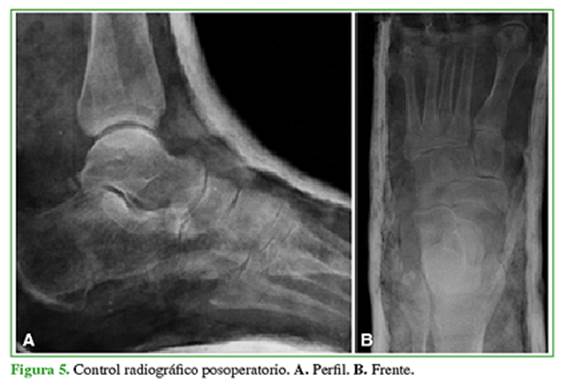

Se decidió realizar la reducción cerrada urgente en el quirófano bajo anestesia general. Para relajar el tendón de Aquiles se efectuó la maniobra de flexión de rodilla. Se aplicó tracción en el eje, acentuando la deformidad, en primer término, para desimpactar y luego llevando el pie a la eversión, se consiguió la reducción. Se constató la adecuada reducción bajo radioscopia (Figura 4), se le colocó una bota corta de yeso, y se tomaron radiografías de control posoperatorias (Figura 5).